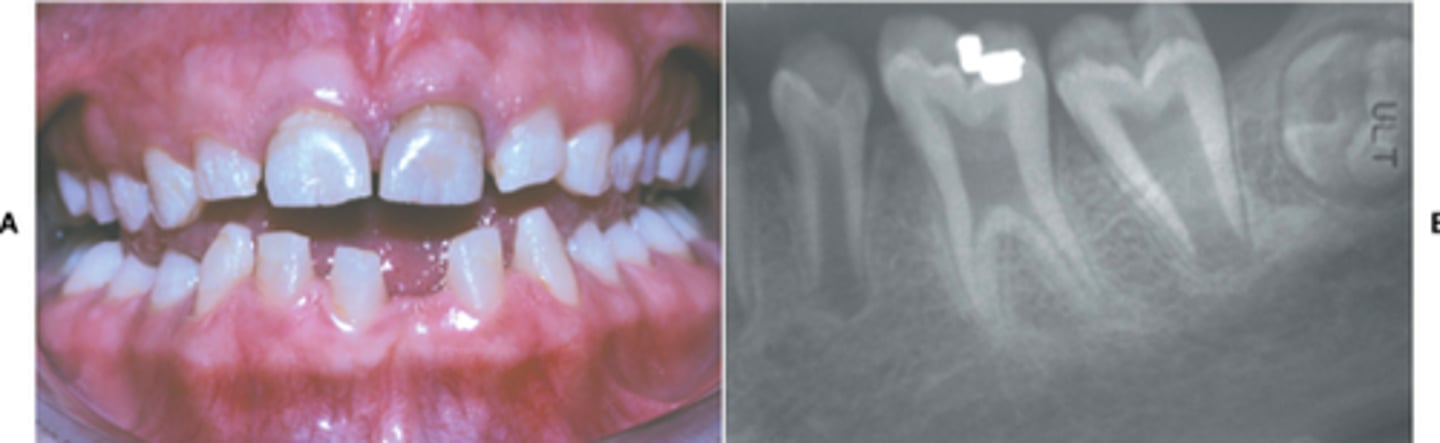

Facial erosion due to acidic beverages

Amelogenesis Imperfecta (xray)